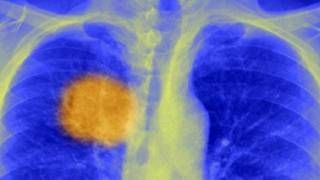

Image copyrightSPLيعتقد علماء أنهم توصلوا إلى أسلوب لـ"توجيه" جهاز المناعة لكي يقتل السرطان، وهو أسلوب ينطبق عليه مصطلح "عقب أخيل"، الذي يشير إلى نقطة ضعف مميتة يؤدي استهدافها إلى انهيار صاحبها مهما بلغت قوته.

فقد طور الباحثون بجامعة كوليدج لندن طريقة لرصد علامات فريدة داخل الورم – "عقب أخيل" الخاص به – بما يسمح للجسد باستهداف المرض.

والمشكلة أن الأورام السرطانية لا تنشأ جميعها من خلايا متماثلة – فهي متحورة بشدة، وتعاني فوضى جينية وتبدو العينات من أماكن مختلفة داخل ورم ما متباينة كما أنها تعمل بشكل مختلف.

وتنمو الأورام السرطانية بشكل يماثل شجرة ذات "جذع" به تحورات تتفرع في شتى الاتجاهات. ويُعرف هذا بعدم التجانس السرطاني.

وقد طورت الدراسة الدولية أسلوبا لاكتشاف تحورات "الجذع" التي تؤدي إلى تغير مضادات المناعة، وهي البروتينات التي تخرج من سطح الخلايا السرطانية.